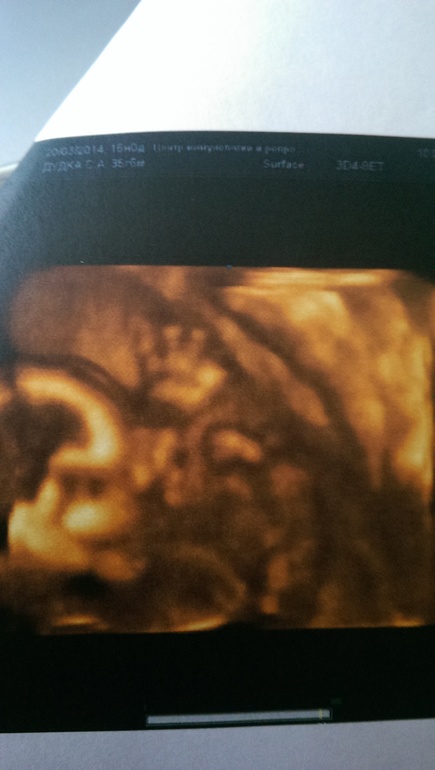

При каждой встрече нам машут ручкой! И еще,наша Пузя - мальчик!

Очень подвижный,настоящий футболист. Показал все,чему он научился: пинаться ножками, сосать пальчик то на ручке,то на ножке, махать ручками,жевать! Вы видели,как малыш в животике жует?Я в этот момент тоже хотела есть)))

И немного фото. Правда с телефона